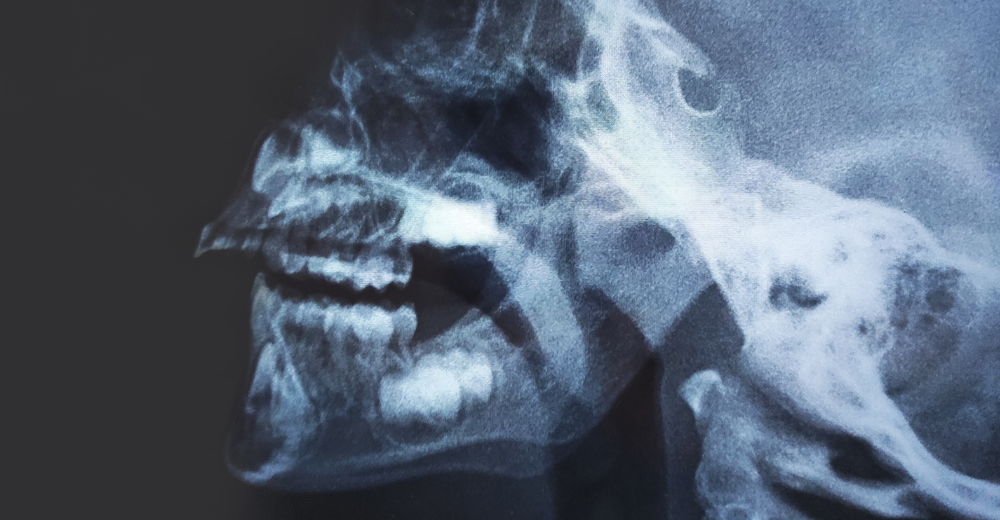

La RX Rinofaringe è un esame diagnostico non invasivo che permette di ottenere immagini dettagliate della rinofaringe, ossia la parte posteriore della cavità nasale. Presso il Poliambulatorio S-Medical Group di Sora, questo esame viene eseguito con apparecchiature all’avanguardia e da professionisti esperti, garantendo un elevato standard di sicurezza e precisione diagnostica. L’utilizzo di raggi X a bassa dose consente di individuare eventuali anomalie o patologie nella zona, aiutando i medici a definire un trattamento personalizzato.

L’acronimo “RX” si riferisce alla radiografia, mentre la rinofaringe è la parte della cavità nasale situata nella parte posteriore del naso e che si estende fino alla gola. La RX Rinofaringe è quindi una radiografia specifica utilizzata per visualizzare questa regione anatomica e diagnosticare eventuali problemi, come polipi, infezioni o malformazioni strutturali.

Grazie all’RX Rinofaringe, è possibile osservare con precisione le ossa, i tessuti molli e le strutture della rinofaringe. Al Poliambulatorio S-Medical Group di Sora, i medici analizzano attentamente le immagini per rilevare eventuali alterazioni anatomiche e anomalie, quali infiammazioni, lesioni o altre condizioni patologiche che possono influire sulla funzionalità respiratoria.

Con l’esame di RX Rinofaringe, è possibile rilevare diverse condizioni patologiche, come infiammazioni croniche, infezioni persistenti, polipi nasali e malformazioni anatomiche. Il nostro team al Poliambulatorio S-Medical Group di Sora è specializzato nella diagnosi di queste condizioni, garantendo un approccio diagnostico preciso e un trattamento efficace.